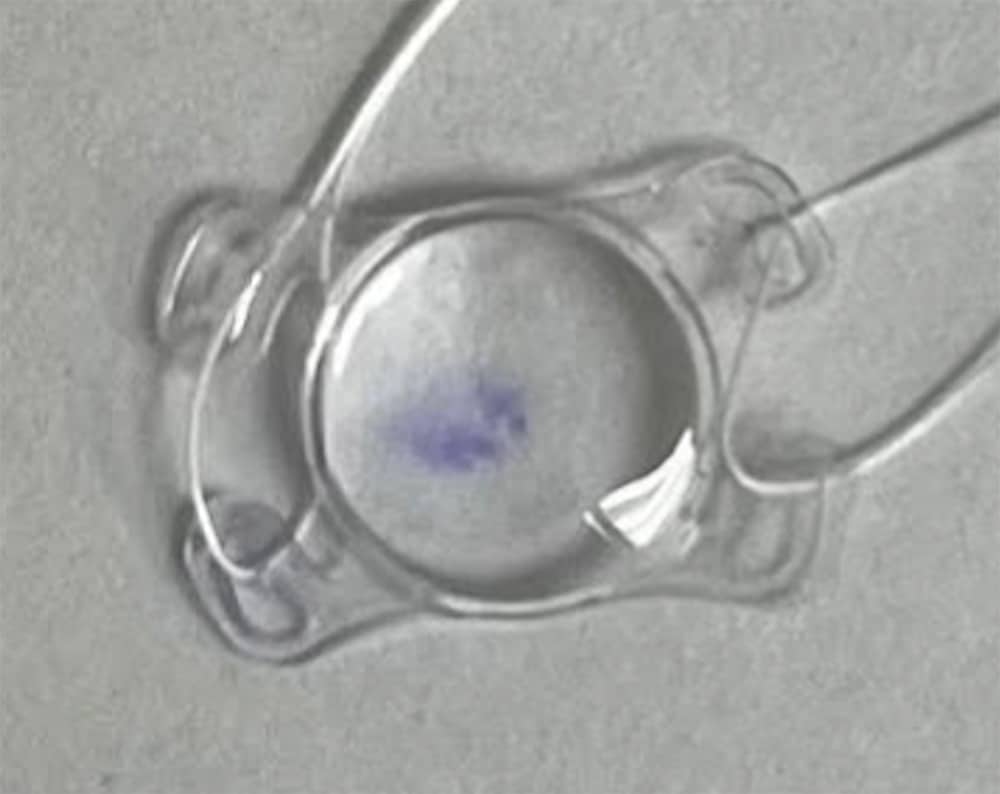

An 80-year-old male was booked for removal of a dislocated IOL and placement of a GorTex sutured Akreos AO60 lens. Before implantation a purple mark from the surgical marking pen was noted on the lens (Fig 1). With irrigation and manual scrubbing there was no clearing of the pigment. The lens was discarded and a new Akreos lens was inserted. Although opacification of the Akreos lens has been reported there are no known reports of staining of the lens with marking pen pigmentation. Care must be taken during surgery to avoid any inadvertent staining of the IOL before implantation.